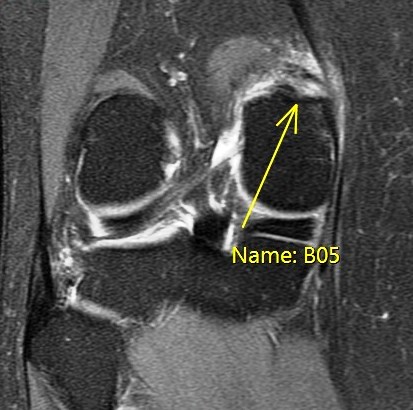

Figure 4 for case Partial tear of the tendon of the medial head of the gastrocnemius muscle ( RID2921 )

Figure 4

Partial tear of the origin.

Partial tear of the tendon of the medial head of the gastrocnemius muscle ( RID2921 )